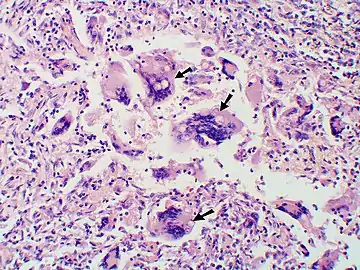

Large, broadly-based budding yeast cells characteristic of Blastomyces dermatitidis in a GMS-stained biopsy section from a human leg.

Once suspected, the diagnosis of blastomycosis can usually be confirmed by demonstration of the characteristic broad based budding organisms in sputum or tissues by KOH prep, cytology, or histology.[27] Tissue biopsy of skin or other organs may be required in order to diagnose extra-pulmonary disease. Blastomycosis is histologically associated with granulomatous nodules.

In disseminated blastomycosis, the large Blastomyces yeast cells translocate from the lungs and are trapped in capillary beds elsewhere in the body, where they cause lesions. The skin is the most common organ affected, being the site of lesions in approximately 60% of cases.[20] The signature image of blastomycosis in textbooks is the indolent, verrucous or ulcerated dermal lesion seen in disseminated disease. Osteomyelitis is also common (12–60% of cases). Other recurring sites of dissemination are the genitourinary tract (kidney, prostate, epididymis; collectively ca. 25% of cases) and the brain (3–10% of cases).[20] 40% of immunocompromised individuals have CNS involvement and present as brain abscess, epidural abscess or meningitis.